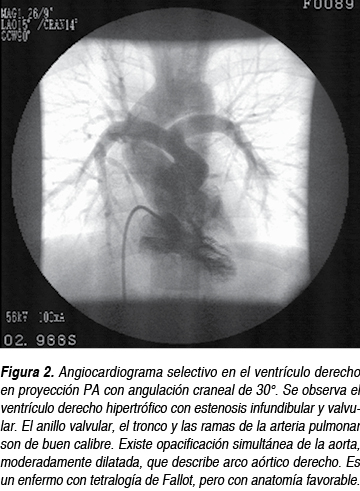

La resonancia magnética y el cateterismo cardiaco (Figura 2) actualmente se usan poco en los casos típicos y el enfermo puede operarse sin ellos (más adelante veremos el estado actual de las indicaciones); cuando se sospechan dañod colaterales, estenosis periférica de ramas, anomalías coronarias o existe alguna duda razonable, se emplea la resonancia magnética o el cateterismo cardiaco, dependiendo de los recursos con los que cuente el centro.